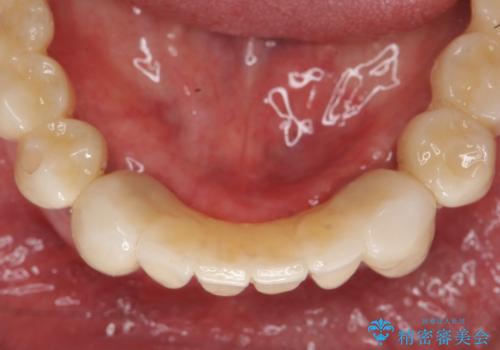

再生治療により良好な歯槽骨の再生が得られ、入れ歯ではなく取り外しの必要のないブリッジによる機能回復を行うことができました。

残すことのできない歯を抜去し、入れ歯になることを回避すべくブリッジ治療を行いますが支台となる歯の歯周病を改善すべく歯周病により溶けた歯槽骨の再生治療を計画します。